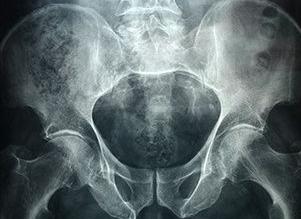

Рентгенографию копчика (обычно вместе с крестцом) выполняют на горизонтальном столе. Существует несколько укладок для ее проведения (несколько положений тела пациента на столе). Выбор укладки всегда остается за врачом-рентгенологом.

Рентген копчика проводится одновременно с обследованием крестцового отдела. В зависимости от проекции, в которой необходимо получить снимки, больной должен занять одно из 3-х положений:

Современной практикой принято делать снимки в прямой и боковой проекциях, так как это дает полную картину возможной травмы хвостового отдела. На прямом снимке хорошо видны позвонки, а на боковом — остистые отростки и расположение позвонков относительно друг друга. Врач может потребовать еще несколько проекций, но, как правило, двух бывает достаточно для постановки диагноза.